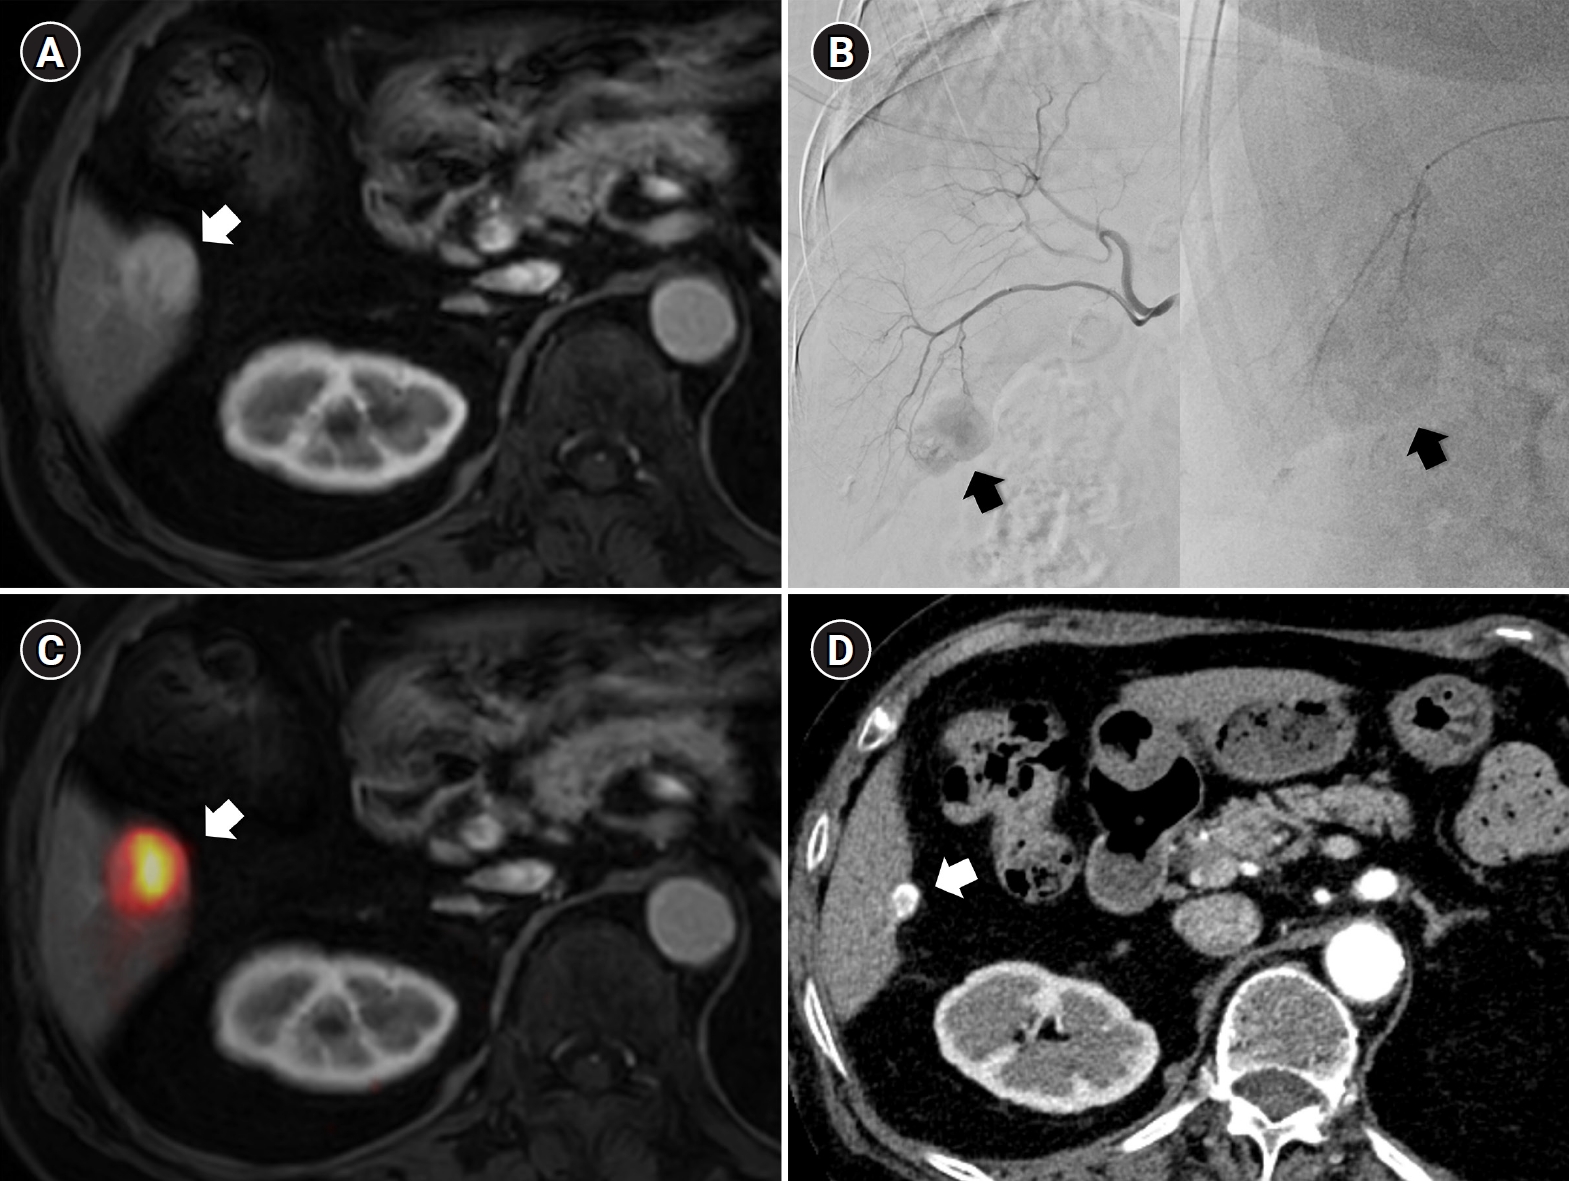

- Original Article Mar 30, 2026 Impact of embolic agents on outcomes of renal angiomyolipoma embolization: a dual-center retrospective cohort study Kun Yung Kim, Minuk Kim, Chang Jin Yoon, et al. Korean J Interv Radiol 2026;31(1):36-42.